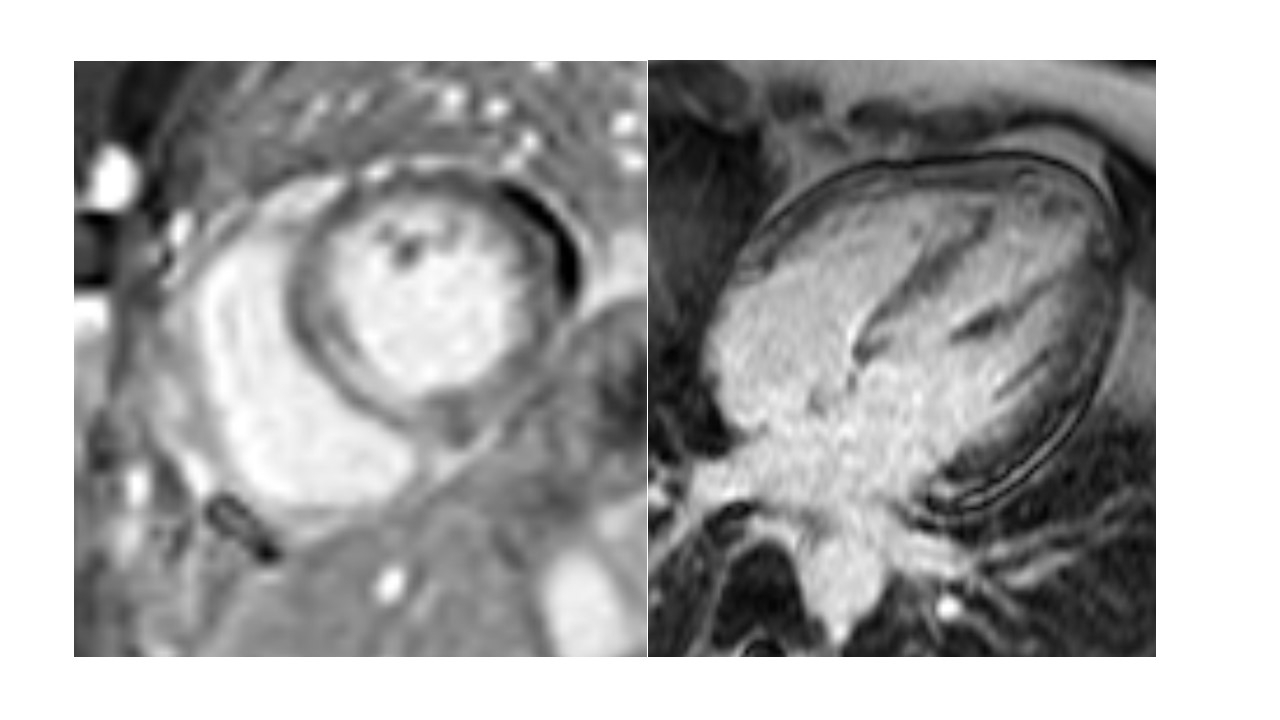

Abstract Body (Do not enter title and authors here): Eosinophilic myocarditis (EM) is a rare inflammatory myocarditis characterized by eosinophilic infiltration of myocardial tissue. Despite the high mortality rate, EM is frequently underdiagnosed and is often first identified in postmortem studies. We share a case of EM as an early manifestation of newly diagnosed eosinophilic granulomatosis polyangiitis (EGPA). The patient is a 46-year-old female with a past medical history of ulcerative colitis and adult-onset asthma who presented to the emergency department with a 2–3-week history of worsening positional chest pain radiating to the left upper extremity. Associated symptoms include 3 months of fatigue, headaches, right foot neuropathy, urticaria, and B-symptoms. Prior to admission, the patient was started on empiric prednisone for presumed EGPA. Initial lab work on admission was notable for elevated troponin (602 ng/L), hyper-eosinophilia (19.5%), thrombocytosis (680K/uL), and elevated ESR (42 mm/h) that have improved since initiation of prednisone. Transthoracic echocardiogram revealed a newly reduced LVEF of 40% with basal and mid-septal wall motion abnormalities. Cardiac catheterization showed normal coronaries confirming the diagnosis of non-ischemic cardiomyopathy. Late gadolinium enhancement in cardiac MRI was seen in basal to mid segments with patchy pericardial enhancement, meeting the Lake Louise criteria for myocarditis. An endomyocardial biopsy showed substantial myocardial infiltration with lymphocytes, histiocytes and eosinophils, confirming the diagnosis of EM. After multidisciplinary team discussion with cardiology and rheumatology, the patient was started on guideline-directed medical therapy for her HFrEF and pulse dose steroids with a prolonged taper and cyclophosphamide. She is tolerating her treatment well. This case highlights the importance of early recognition, comprehensive assessment and targeted treatment for EM depending on its underlying etiology. In the case of autoimmune dysfunction, it involves a combination of immunosuppressive and symptomatic therapy. Ongoing research is crucial to enhance our understanding and improve clinical outcomes, like arrhythmias and cardiogenic shock, for this complex condition.